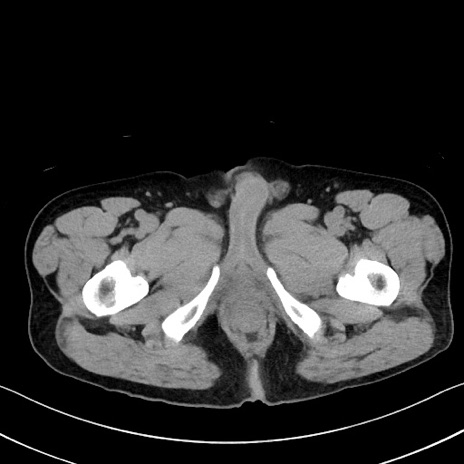

冠状断像